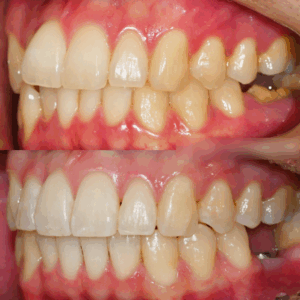

앞니 뻐드렁니 및 총생 반대교합 등 다양한 문제가 있을 때 교정치료 어떻게?

입을 열었을 때 치열이 어지럽게 놓여있다면 여러모로 신경이 쓰이게 됩니다. ​ 외적으로 안 좋은 영향을 줄 뿐만이 아닌, 기능적 측면에도 악영향을 줘서 건강을 해칠 수 있습니다. ​ 비뚤어져 있는 치열을…